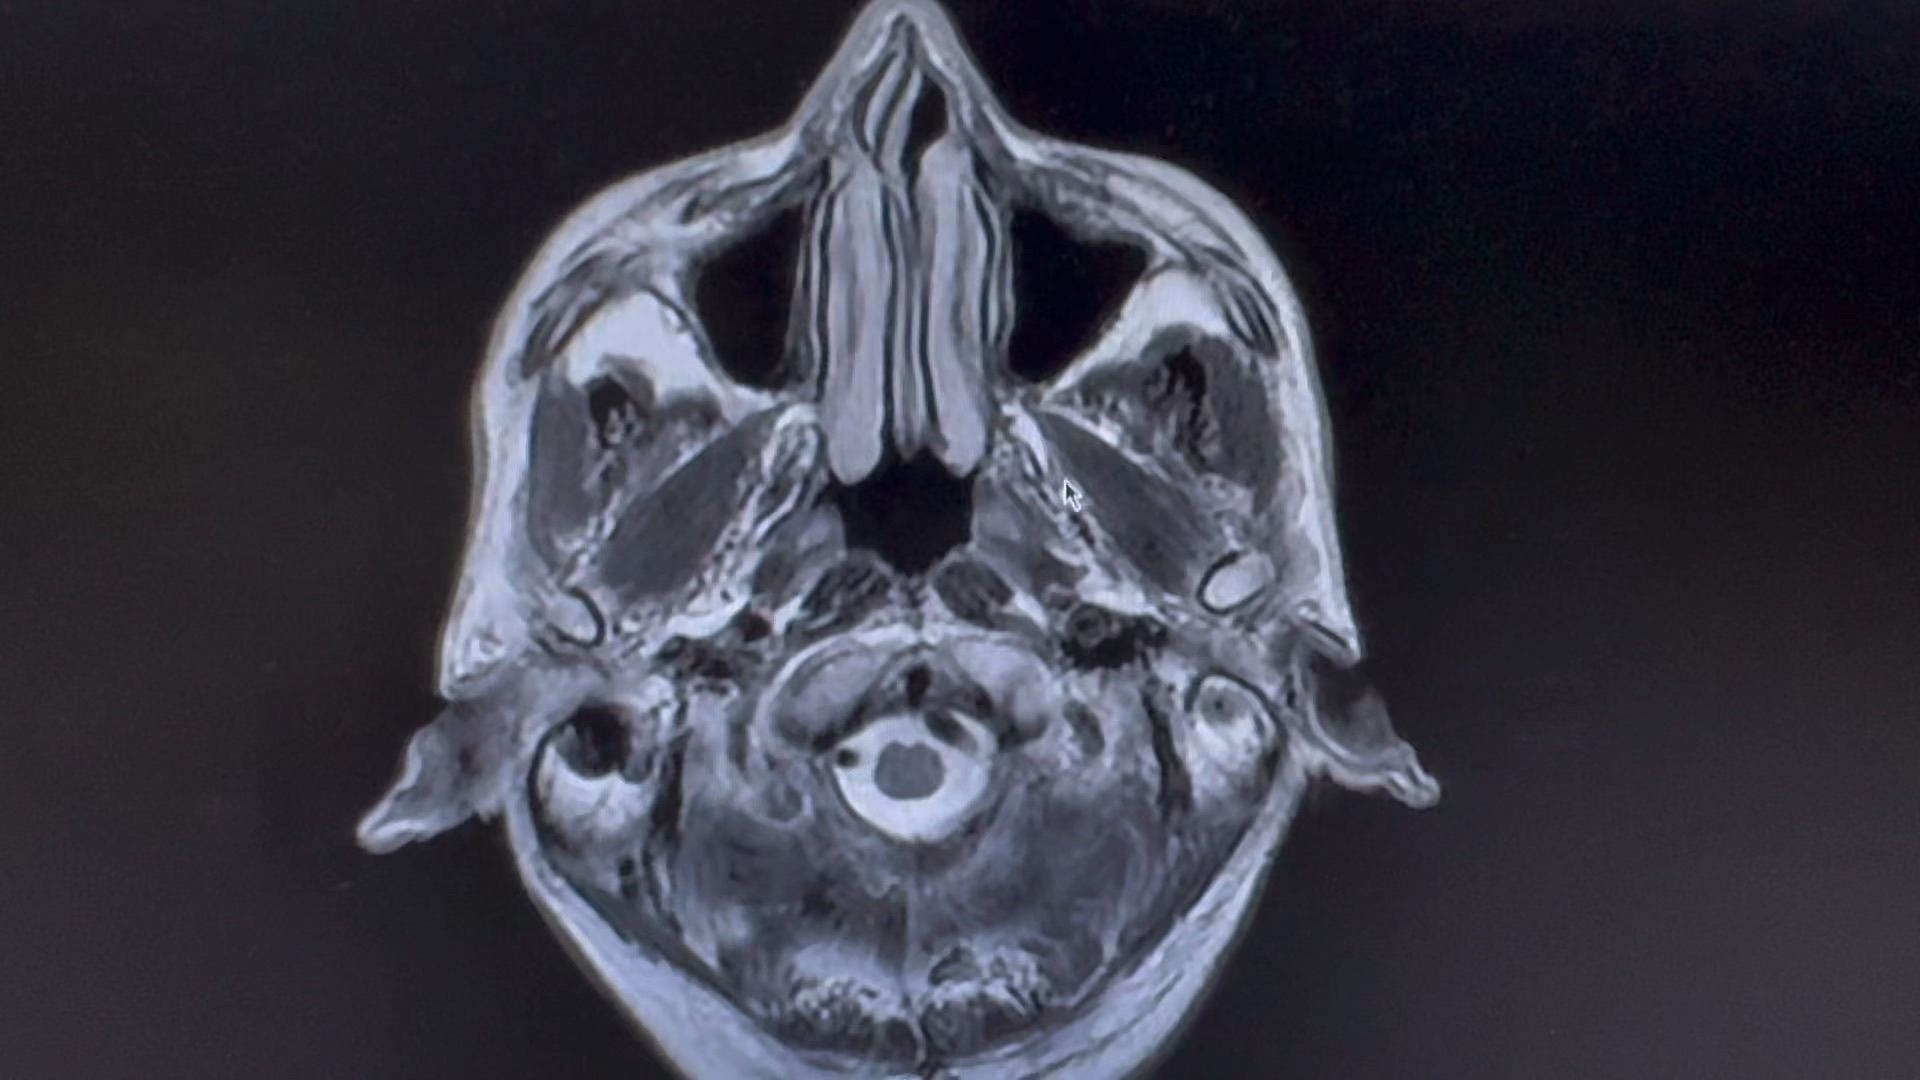

男,66 岁

突发剧烈头疼,呕吐伴意识模糊数小时。

一人在家,家属下班后发现患者情况不对,拨打 120 急诊入院,已转入脑介入科。